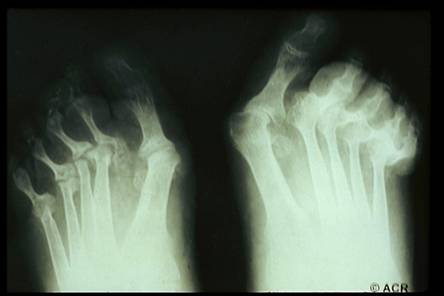

Artrite reumatoide

È una malattia sistemica del connettivo ad elettiva localizzazione poliarticolare, ad andamento cronico e progressivo, con carattere erosivo, a tendenza anchilosante, caratterizzata dalla presenza sierica di anticorpi anti-immunoglobuline denominati fattori reumatoidi.

Precoce interessamento di mani e piedi: deformazione a collo di cigno, a boutonniere, dita a martello, mani a colpo di vento;

Deformità articolari;

Alterazioni radiologiche (osteoporosi distrettuale ed erosioni alle radiografie di mani e polsi

Segni radiologici

1) Precoci:

Tumefazione dei tessuti molli

Osteoporosi periarticolare

Periostite

Erosioni dei margini articolari

Cisti subarticolari

2) Avanzati:

Rime articolari ristrette

Irregolarità delle superfici articolari

Sublussazioni articolari

Osteoporosi generalizzata

Alterazioni degenerative secondarie

Anchilosi ossea